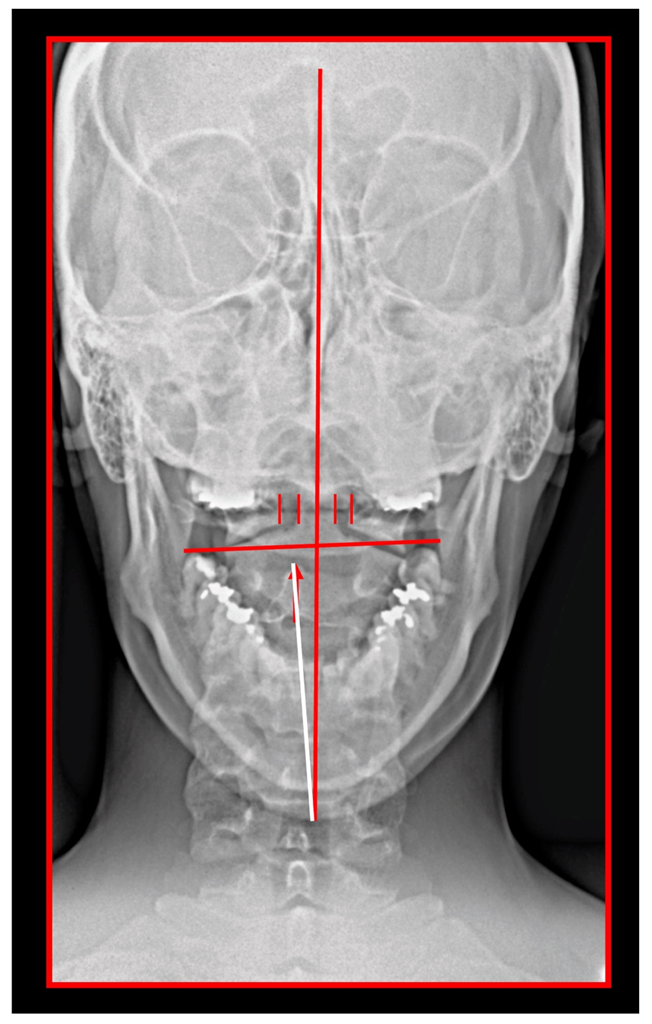

The Importance of the Skeletal Midline

- Rocabado, M.; Gutierrez, R.; Gutierrez, M.F.; Gutierrez, M.J. Case report: Anterior open bite correction treatment by dental treatment and physical therapy through craniocervical mandibular and occlusal stabilization. Cranio 2021, 10, 1–6. [Google Scholar] [CrossRef]